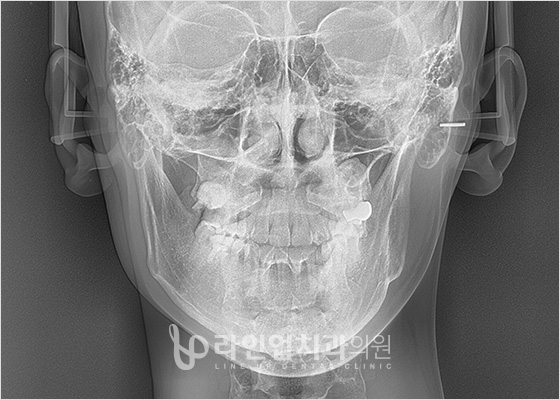

前后照片

Before

After